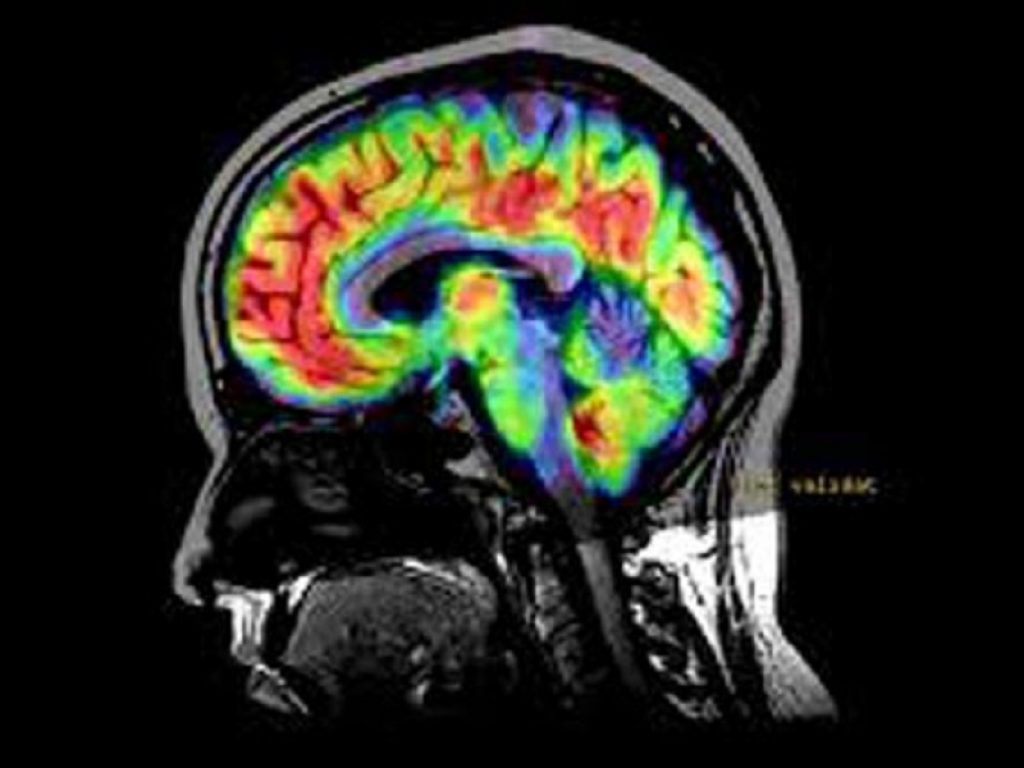

I cavernomi cerebrali sono delle malformazioni dei vasi sanguigni del cervello e del midollo spinale. Hanno una forma a grappolo, simile ai lamponi, e gli “acini” pieni di sangue sono chiamati “caverne”. La parete di tali caverne è particolarmente fragile e permeabile, a differenza della parete dei vasi sanguigni normali. La conseguenza patologica di tale anomalia anatomica è che i cavernomi sanguinano facilmente, provocando nei pazienti deficit neurologici, crisi epilettiche, mal di testa ricorrenti e, nei casi peggiori, ictus emorragico. Una volta effettuata la diagnosi tramite risonanza magnetica e analisi genetica delle mutazioni responsabili della malattia, l’unico trattamento possibile finora è la rimozione chirurgica tramite craniotomia, una procedura invasiva e particolarmente critica se il paziente è un bambino o se il cavernoma è ubicato in un’area cerebrale delicata o nel midollo spinale.

Il nostro corpo contiene diversi tipi di vasi sanguigni (vene, arterie e capillari) composti in buona parte da cellule endoteliali. Le cellule endoteliali costituiscono la parete interna del vaso esposta al sangue e presentano una grande eterogeneità molecolare che dipende dal tipo di vaso e di organo in cui risiedono. Le recenti tecnologie genomiche a singola cellula permettono di determinare la sequenza delle molecole di RNA che singola cellula contiene e quindi di definire l’eterogeneità delle cellule contenute in un tessuto. Nel caso specifico della patologia CCM – dove la mutazione patologica avviene nelle cellule endoteliali – tale tecnica consente di studiare l’eterogeneità delle cellule endoteliali dei vasi cerebrali patologici rispetto a quelli normali.